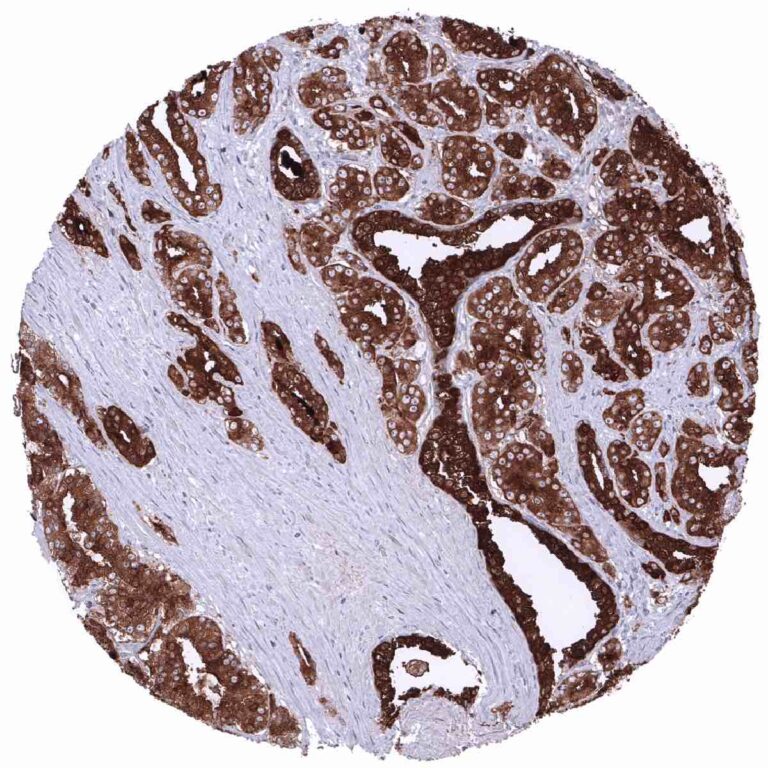

Positive control = Prostate: The epithelial cells of the prostate glands must show a strong cytoplasmic staining. Due to leakage of the antigen in the vicinity of the prostate glands, adjacent stroma cells may display a weak to moderate staining reaction.